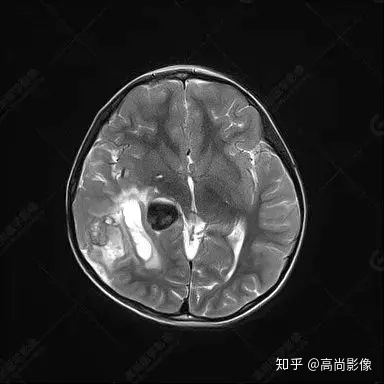

右側(cè)顳葉腫瘤切除術(shù)后(具體不詳):右側(cè)顳部骨質(zhì)不連續(xù)呈術(shù)后改變,右側(cè)顳葉術(shù)區(qū)見片狀長T1長T2信號(hào)影,F(xiàn)LAIR呈低信號(hào);術(shù)區(qū)后方右側(cè)顳枕葉見一巨大占位性病變影,邊界欠清,大小約6.2×5.8×4.3cm(前后×左右×上下),信號(hào)不均勻,T1WI呈等稍低信號(hào)間雜少許高信號(hào),T2WI呈高稍低混雜信號(hào),DWI示部分病灶彌散受限,相應(yīng)ADC圖減低,磁敏感序列見部分呈極低信號(hào),增強(qiáng)掃描可見明顯不均勻強(qiáng)化,鄰近硬腦膜及小腦幕增厚并明顯強(qiáng)化;另延髓右前方及右側(cè)橋小腦角區(qū)見一不規(guī)則形異常信號(hào)影,大小約3.2×1.3×3.7cm(左右×前后×上下),呈長T1稍長T2信號(hào),F(xiàn)LAIR呈等信號(hào),DWI未見受限,增強(qiáng)后明顯均勻強(qiáng)化,鄰近腦膜明顯強(qiáng)化。鄰近腦實(shí)質(zhì)及右側(cè)顳角明顯受壓;左側(cè)大腦半球未見局灶性信號(hào)異常,中線結(jié)構(gòu)稍左移。

右側(cè)顳葉腫瘤切除術(shù)后:現(xiàn)術(shù)區(qū)后方右側(cè)顳枕葉及延髓右前方占位,右側(cè)顳枕部硬腦膜及小腦幕明顯強(qiáng)化,結(jié)合既往影像資料,考慮為胚胎源性惡性腫瘤,如非典型畸胎樣/橫紋肌樣瘤(AT/RT)或原始神經(jīng)外胚層腫瘤(PNET)。